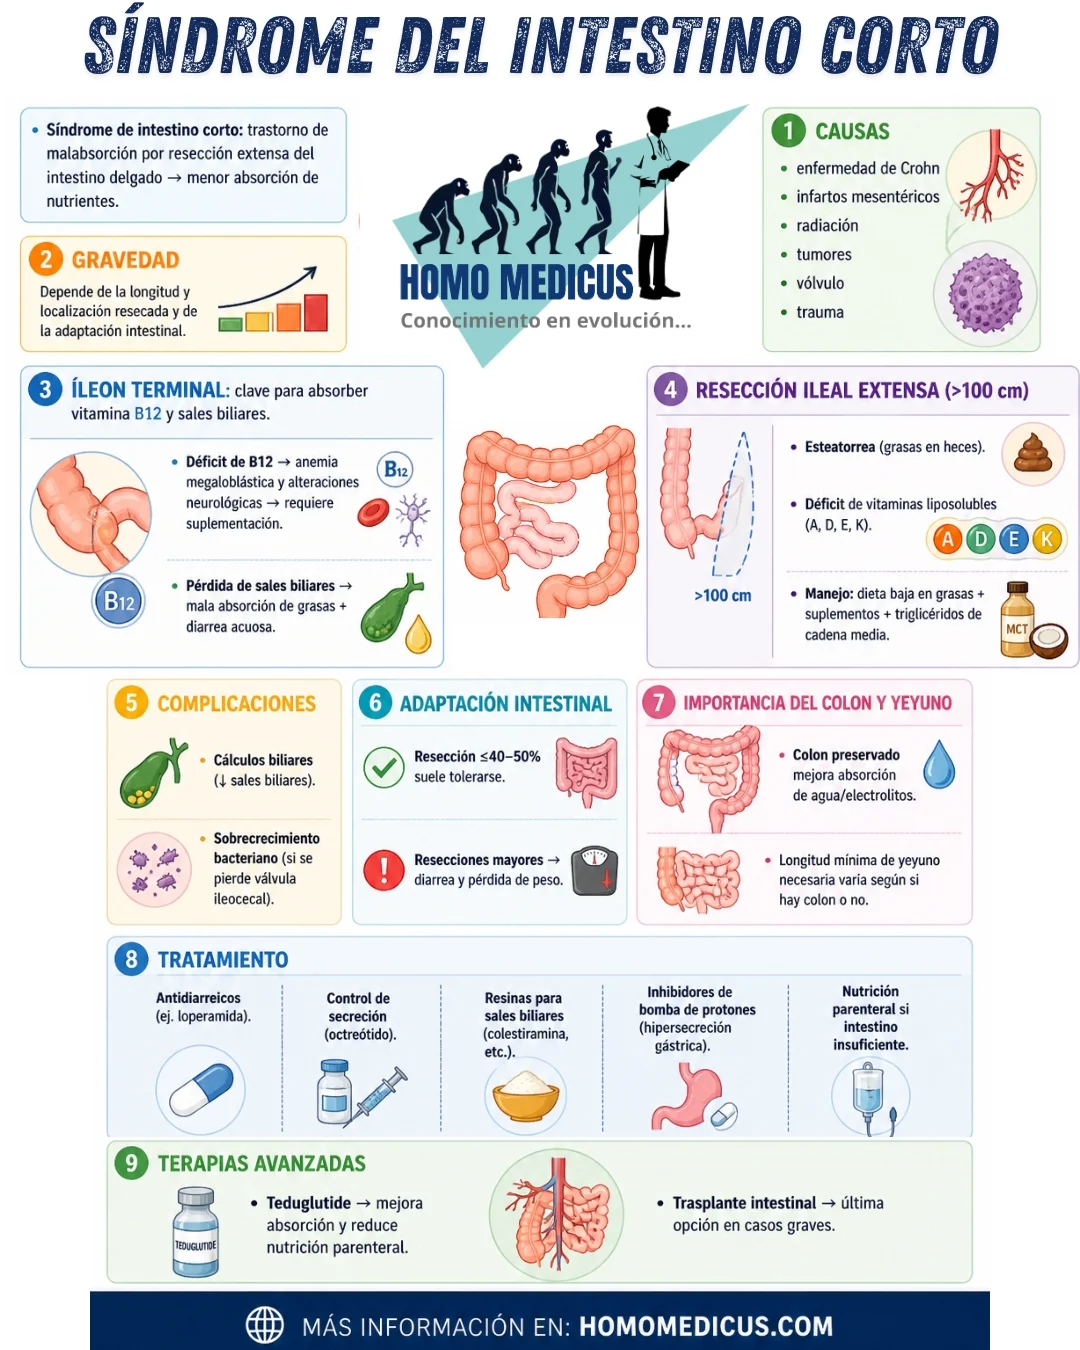

El síndrome de intestino corto es una condición malabsortiva que surge como consecuencia de la resección quirúrgica de segmentos significativos del intestino delgado. Esta afección se asocia con una capacidad reducida para absorber nutrientes de los alimentos debido a la disminución de la superficie intestinal disponible. Las causas más comunes de resección intestinal en adultos incluyen enfermedades inflamatorias crónicas como la enfermedad de Crohn, infartos mesentéricos, enteritis por radiación, vólvulo intestinal, resección de tumores y traumas abdominales. La gravedad del síndrome de intestino corto y la naturaleza de la malabsorción dependen en gran medida de la longitud y la ubicación de la resección, así como de la capacidad del intestino restante para adaptarse a la nueva situación y realizar las funciones absorbentes de manera eficiente.

Una de las resecciones más frecuentes en este contexto es la del íleon terminal, que juega un papel crucial en la absorción de nutrientes. El íleon terminal es la última porción del intestino delgado y se encarga de la absorción de sales biliares y vitamina B12, dos componentes esenciales para la digestión y absorción adecuada de grasas y otras sustancias. Cuando se reseca esta porción del intestino, los pacientes experimentan malabsorción tanto de las sales biliares como de la vitamina B12. La deficiencia de vitamina B12 es especialmente significativa, ya que esta vitamina es crucial para la formación de glóbulos rojos y la función del sistema nervioso. En pacientes que tienen bajos niveles de vitamina B12 en suero o que han tenido una resección de más de 50 cm de íleon, es necesario administrar inyecciones de vitamina B12 por vía subcutánea o intramuscular de forma mensual para prevenir la anemia megaloblástica y otros trastornos neurológicos asociados con su deficiencia.

Por otro lado, la malabsorción de sales biliares que resulta de la resección del íleon terminal afecta la capacidad del cuerpo para emulsificar y absorber las grasas. Las sales biliares son esenciales para la digestión de las grasas, ya que facilitan la formación de micelas, estructuras que permiten la absorción de los lípidos en el intestino delgado. Cuando el intestino delgado no puede recuperar suficientes sales biliares debido a una resección del íleon, estas sales biliares se pierden en las heces, lo que lleva a la estimulación de la secreción de líquidos por parte del colon, causando diarrea acuosa. Esta condición puede ser tratada mediante la administración de resinas que se unen a las sales biliares, como colestiramina (2 a 4 g por día), colestipol (2 g por día) o colesevelam (625 mg por día), las cuales se toman generalmente con las comidas. Estas resinas ayudan a secuestrar las sales biliares, reduciendo su pérdida y, por lo tanto, controlando la diarrea.

Cuando la resección del íleon supera los 100 cm, los problemas se agravan, ya que se reduce significativamente el depósito de sales biliares, lo que empeora la absorción de grasas y resulta en esteatorrea, una condición en la que las heces contienen un exceso de grasa no digerida. La esteatorrea es un signo claro de malabsorción de grasas, y se acompaña a menudo de la malabsorción de vitaminas liposolubles como la vitamina A, vitamina D, vitamina E y vitamina K, esenciales para una variedad de procesos biológicos, incluyendo la visión, la salud ósea, la función inmune y la coagulación sanguínea. Para tratar la esteatorrea y las deficiencias vitamínicas asociadas, se recomienda seguir una dieta baja en grasas, ya que la limitación en el consumo de grasas reduce la cantidad de grasa no digerida en las heces. Además, es fundamental suplementar con vitaminas liposolubles y triglicéridos de cadena media, los cuales no requieren la formación de micelas para su absorción, lo que los hace una fuente alternativa de grasas que el intestino puede absorber más fácilmente.

Otra complicación común en pacientes con resección ileal es la formación de cálculos biliares. La disminución de las sales biliares, que son necesarias para disolver el colesterol, puede llevar a la formación de piedras en la vesícula biliar debido a un aumento en la concentración de colesterol en la bilis. Estos cálculos pueden causar obstrucción y dolor abdominal, lo que agrava aún más el cuadro clínico.

Cuando los pacientes han sufrido la resección de la válvula ileocecal, una estructura que conecta el íleon con el colon, puede desarrollarse sobrecrecimiento bacteriano en el intestino delgado, lo que agrava aún más la malabsorción. La válvula ileocecal tiene la función de prevenir el paso de bacterias del colon hacia el intestino delgado. Su pérdida aumenta la posibilidad de que las bacterias del colon se reubiquen en el intestino delgado, lo que resulta en una proliferación bacteriana anormal. Este sobrecrecimiento bacteriano puede interferir con la digestión y absorción de nutrientes, lo que contribuye a la diarrea, la distensión abdominal y la malnutrición.

La resección de hasta un 40-50% de la longitud total del intestino delgado generalmente es bien tolerada por los pacientes, ya que el intestino restante tiene la capacidad de adaptarse y realizar las funciones digestivas y absorbentes de manera adecuada. Sin embargo, cuando se realiza una resección más extensa, puede ocurrir lo que se conoce como síndrome de intestino corto, una condición malabsortiva caracterizada principalmente por pérdida de peso y diarrea, debido a la incapacidad del intestino restante para absorber nutrientes, agua y electrolitos en cantidades suficientes. La severidad de este síndrome depende de la longitud y la ubicación de la resección, así como de la capacidad del intestino restante para adaptarse a la pérdida de función.

En casos donde se ha preservado el colon, la resección de hasta 100 cm de yeyuno proximal (la porción del intestino delgado que se encuentra inmediatamente después del duodeno) puede ser suficiente para mantener una nutrición adecuada a través de una dieta baja en grasas y rica en carbohidratos complejos. El yeyuno proximal tiene una gran capacidad de absorción de nutrientes, y, aunque la malabsorción de líquidos y electrolitos puede ser significativa, los pacientes pueden seguir manteniendo una nutrición oral adecuada. En cambio, en pacientes en los que se ha extirpado el colon, al no tener la capacidad de reabsorber el agua y los electrolitos que normalmente ocurriría en esta parte del tracto gastrointestinal, se requiere generalmente una porción mayor del yeyuno proximal para que el intestino restante sea capaz de cumplir con las necesidades nutricionales. En estos casos, la resección de al menos 200 cm de yeyuno proximal es típicamente necesaria para mantener una nutrición exclusivamente oral.

El tratamiento del síndrome de intestino corto se centra en minimizar la malabsorción y controlar los síntomas gastrointestinales, como la diarrea, que son comunes debido a la alteración del tránsito intestinal y la absorción deficiente de líquidos. Los fármacos antidiarreicos como loperamida (2 a 4 mg por vía oral tres veces al día) son eficaces para reducir el volumen de la diarrea al disminuir la motilidad intestinal, lo que permite una mejor absorción de líquidos y nutrientes. Adicionalmente, el octreótido, un análogo de la somatostatina, ha demostrado ser útil para reducir el tiempo de tránsito intestinal y la secreción de fluidos y electrolitos, lo que ayuda a controlar tanto la diarrea como los déficits de líquidos y electrolitos en estos pacientes.

Una de las complicaciones más comunes que se presenta en las primeras fases tras una resección intestinal significativa es la hipersecreción gástrica, debido a la pérdida del feedback negativo que normalmente se realiza entre el intestino y el estómago. Esta hipersecreción puede agravar la malabsorción y el riesgo de úlceras gástricas. Por lo tanto, los pacientes que han sufrido una resección extensa del intestino delgado deben recibir tratamiento con inhibidores de la bomba de protones, que ayudan a reducir la producción de ácido gástrico y, por ende, a controlar los síntomas y evitar complicaciones adicionales.

Para los pacientes en los que el yeyuno restante es insuficiente para garantizar una absorción adecuada de nutrientes, es casi siempre necesario recurrir a la nutrición parenteral (es decir, la administración intravenosa de nutrientes). En general, los pacientes que tienen menos de 100-200 cm de yeyuno proximal restante requieren nutrición parenteral de manera crónica, ya que el intestino restante no puede proporcionar suficiente absorción para mantener los niveles adecuados de nutrientes, agua y electrolitos.

En cuanto a los tratamientos más recientes, el teduglutide, un análogo recombinante del péptido glucagón tipo 2, ha sido aprobado por la FDA para el tratamiento del síndrome de intestino corto. Este fármaco actúa estimulando el crecimiento del intestino delgado y mejorando la absorción de nutrientes, lo que reduce la dependencia de la nutrición parenteral. En ensayos clínicos, el teduglutide ha mostrado reducir la necesidad de nutrición parenteral en pacientes con síndrome de intestino corto, lo que mejora significativamente la calidad de vida y reduce las complicaciones asociadas con la nutrición intravenosa a largo plazo.

En los casos más graves de síndrome de intestino corto, donde las intervenciones médicas no son suficientes, el trasplante de intestino delgado se considera una opción. Sin embargo, el trasplante de intestino delgado sigue siendo una opción de último recurso, ya que tiene una tasa de supervivencia del injerto a los 5 años de aproximadamente un 40%. Este procedimiento se realiza principalmente en pacientes que desarrollan problemas graves derivados de la dependencia de la nutrición parenteral, como infecciones recurrentes, disfunción hepática por la nutrición intravenosa a largo plazo o un deterioro generalizado de la calidad de vida.